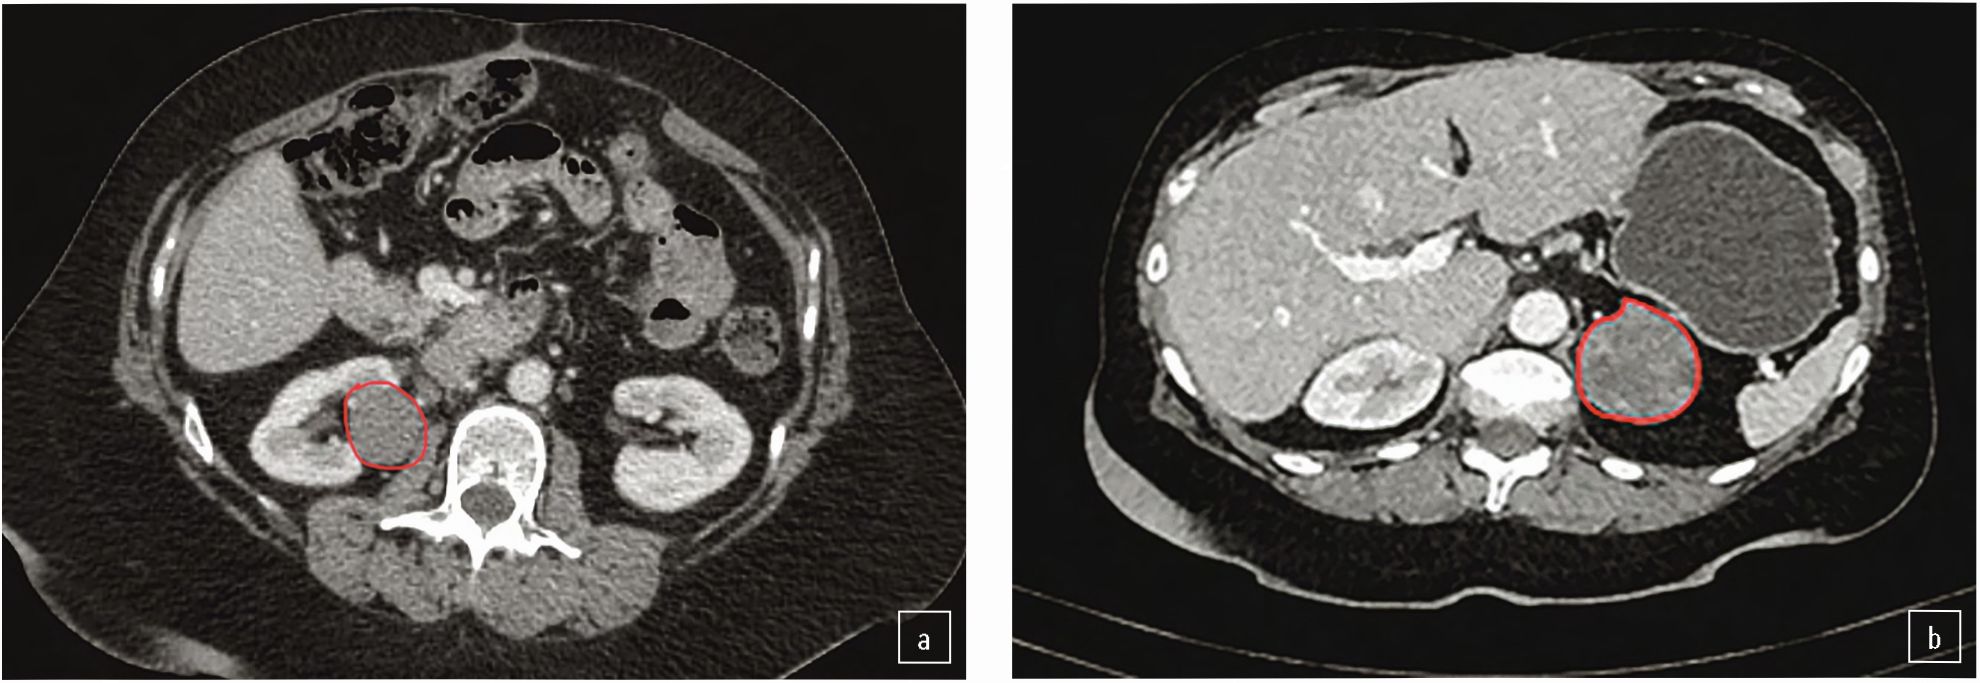

При контрольном обследовании в октябре 2021 г. выявлены образования в правой почке и левом надпочечнике (рис. 2).

Рис. 2. КТ органов брюшной полости от 10.2021: а – образование средней трети почки 30×28,5 мм; b – образование левого надпочечника 28×25 мм.

Fig. 2. Abdominal CT scan dated October 2021: a – a mass in the middle third of the kidney of 30×28.5 mm; b – left adrenal gland mass of 28×25 mm.

С учетом прогрессирования заболевания и наличия экспрессии опухолью рецепторов к соматостатину принято решение добавить к уже проводимой терапии митотаном пролонгированную форму аналога соматостатина – октреотид Депо/лонг в дозе 40 мг внутримышечно 1 раз в 28 дней.